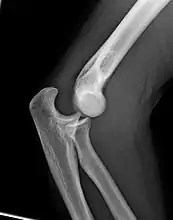

The elbow undergoes dynamic development of ossification centers through infancy and adolescence, with the order of both the appearance and fusion of the apophyseal growth centers being crucial in assessment of the pediatric elbow on radiograph, in order to distinguish a traumatic fracture or apophyseal separation from normal development. The order of appearance can be understood by the mnemonic CRITOE, referring to the capitellum, radial head, internal epicondyle, trochlea, olecranon, and external epicondyle at ages 1, 3, 5, 7, 9 and 11 years. These apophyseal centers then fuse during adolescence, with the internal epicondyle and olecranon fusing last. The ages of fusion are more variable than ossification, but normally occur at 13, 15, 17, 13, 16 and 13 years, respectively.[16] In addition, the presence of a joint effusion can be inferenced by the presence of the fat pad sign, a structure that is normally physiologically present, but pathologic when elevated by fluid, and always pathologic when posterior.[17]

Fractures

There are three bones at the elbow joint, and any combination of these bones may be involved in a fracture of the elbow. Patients who are able to fully extend their arm at the elbow are unlikely to have a fracture (98% certainty) and an X-ray is not required as long as an olecranon fracture is ruled out.[23] Acute fractures may not be easily visible on X-ray.